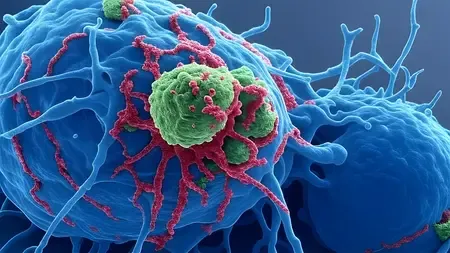

A recent study reveals alarming findings about agricultural dust and its potential dangers to gut health in animal agriculture workers. This research highlights the need to understand the broader…